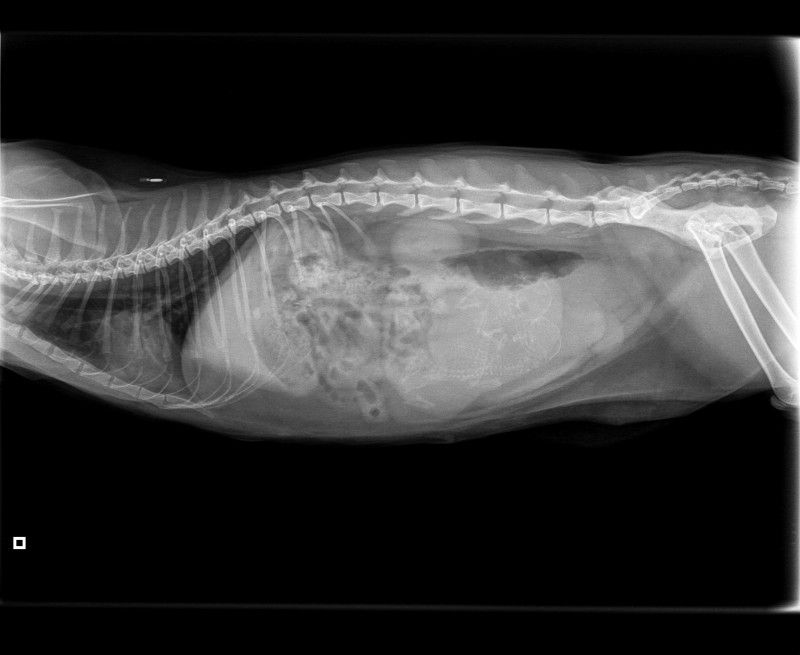

Vrjddag 24 april zijn wij met Mirre naar onze dierenarts Zuiderkaag in Schagen geweest om een foto te maken. Omdat Mirre niet zo heel dik is zou ze zwanger kunnen zijn van 1 kitten, we waren bang dat het dan te groot zou worden. Gelukkig blijkt uit de foto dat ze zwanger is van 2 kittens.